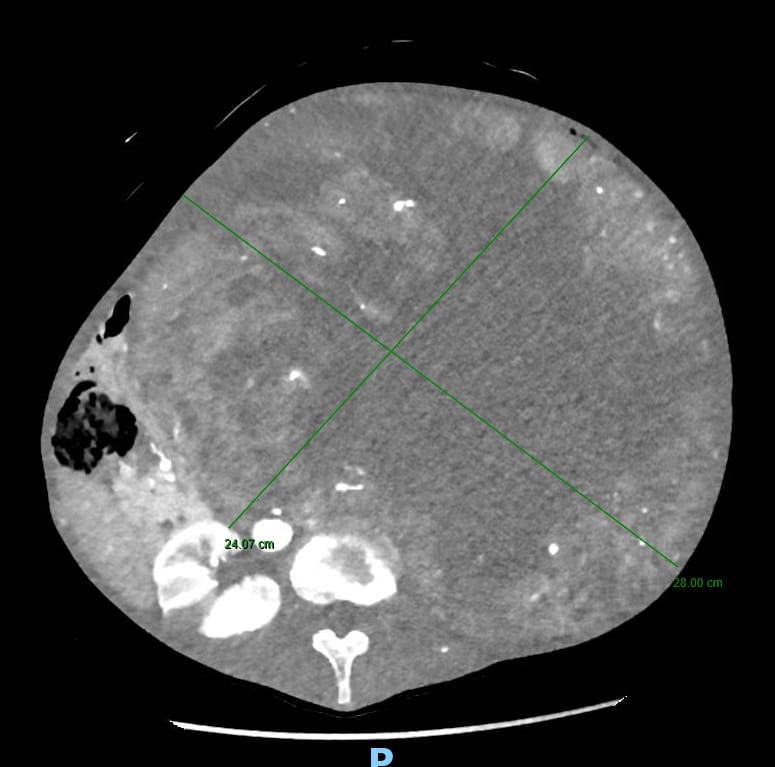

Tutto è iniziato da un disturbo apparentemente comune: la stipsi. La paziente si era infatti rivolta per la risoluzione del problema al Prof. Guido Sciaudone, direttore della SC di Chirurgia Generale, che la aveva visitata presso l’ambulatorio di Chirurgia Colo-Rettale ed Oncologica della ASREM da lui diretto. Tuttavia, alla visita clinica era da subito apparso evidente che il sintomo stipsi era secondario alla presenza di una voluminosa massa addominale di dimensioni spropositate che i successivi accertamenti diagnostici rivelavano essere a partenza dal rene sinistro. Tale massa – paragonabile a un grosso cocomero – occupava ormai l’intera cavità addominale, comprimendo oltre all’intestino tenue ed al colon, organi importanti quali il fegato, la milza, lo stomaco, il pancreas ed il duodeno e compromettendo la circolazione sanguigna di tali strutture.

L’operazione, delicatissima, che ha richiesto estrema precisione, ha previsto diverse procedure integrate: la nefrectomia totale con l’asportazione del rene inglobato nella massa di verosimile natura eteroplastica (si è in attesa dell’esame istologico definitivo), la colectomia subtotale (cioè la rimozione di gran parte del colon in quanto ischemico in seguito all’occlusione cronica ed alla sofferenza vascolare dovuta alla compressione dei vasi da parte della massa) ed il confezionamento di una derivazione intestinale esterna per permettere la canalizzazione.